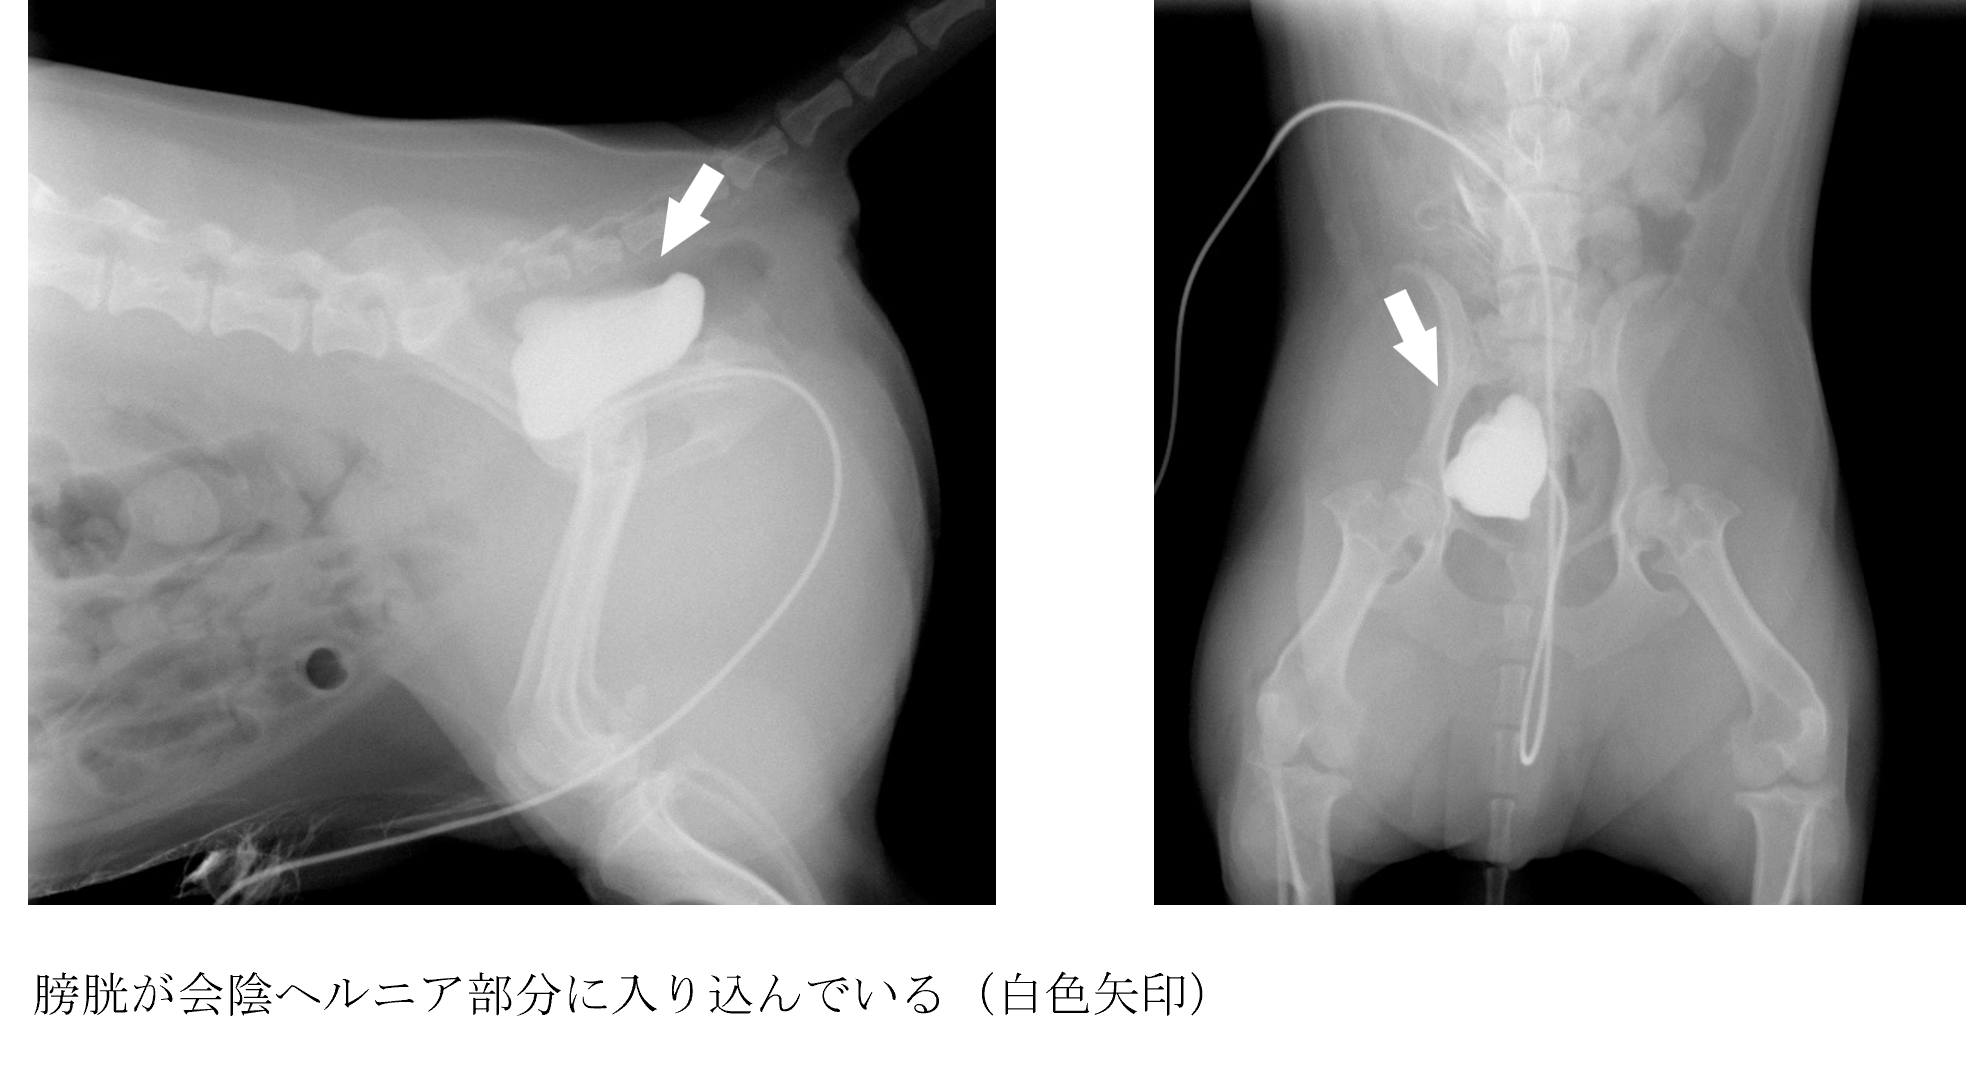

各種検査より会陰ヘルニア部分に膀胱が入ってしまったことによる排尿障害と診断しました。

相談した結果、膀胱の整復、会陰ヘルニアの整復、直腸固定・精管固定をする手術になりました。